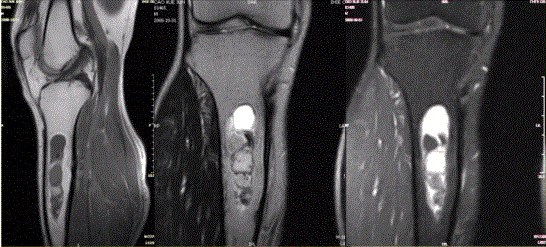

问题 患者女,20岁,右小腿疼痛1周。行双小腿正侧位CR,并行双小腿CT及MR扫描,见下图。 对于此病变的征象,描述不正确的是

选项 A.双侧胫骨骨干不规则膨胀性溶骨破坏 B.病灶边缘清楚,可见硬化缘 C.病灶呈磨砂玻璃样密度 D.在T1WI与T2WI上均表现为低信号,提示为纤维组织 E.病灶内可见多发囊状长T1,长T2信号影,为液化坏死区,提示病变为恶性病变

答案 E